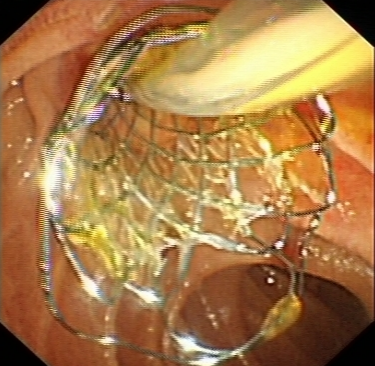

對于無法手術(shù)切除的膽管或胰腺惡性腫瘤導(dǎo)致的梗阻性黃疸,可以進(jìn)行ERCP下膽道支架植入,以緩解梗阻性黃疸癥狀,提高患者生活質(zhì)量。通過光動(dòng)力、射頻消融等治療,還可以控制腫瘤的生長,提高膽道支架的通暢期,延長患者生存時(shí)間。

d71ec809c9b54414b82faa0c0a571f2d.Png  8c01f33631a64260a4c33b5510d217a1.Png

膽道惡性梗阻膽道支架置入